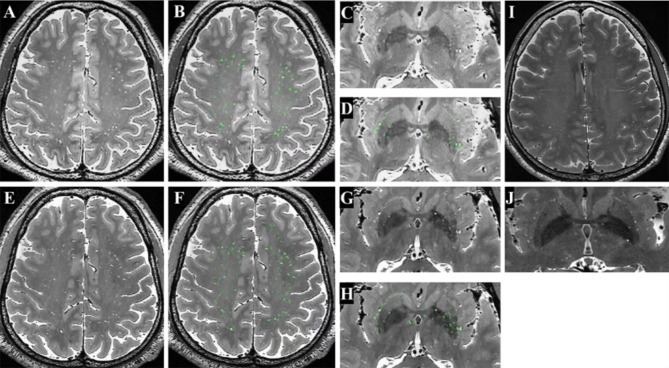

Method: A total of seventeen subjects underwent three-dimensional (3D) T1- and T2-weighted imaging on both 3-T and 5-T MRI systems. Twelve of these subjects underwent quantitative analysis of PVS in the semioval center (SOC) and basal ganglia (BG), with comparisons made between the two systems using paired-sample Wilcoxon tests. Additionally, high-resolution 5-T images were acquired for five other participants to examine the detailed anatomy of PVS in the SOC, BG, and cerebral cortex.

Results: Compared with 3-T MRI, 5-T MRI detected more PVS in the SOC and BG [39.5 (32.0-63.0) vs. 56.5 (44.0-75.5) and 49.5 (27.0-55.8) vs. 65.5 (53.0-72.0)] with p-values of 0.002 and 0.004, respectively. In these two regions, the PVS tortuosity, defined as the ratio of the actual path length to the straight-line distance between the start and end points of the PVS, was lower at 3-T compared to 5-T (p = 0.012 for the SOC and p = 0.006 for the BG). The length of PVS in the SOC on 5-T was longer than those on 3-T [4.6 mm (3.9-6.3 mm) vs. 5.1 mm (4.6-6.7 mm), p = 0.049]. In addition, the 5-T MRI provided enhanced visualization of the morphology of PVS in vivo, and improved the depiction of PVS across various brain regions, especially in the cortex, illustrating their course and associated small vessels.

Conclusions: 5-T MRI notably enhanced the visualization of PVS compared to 3-T, particularly in its ability to depict PVS anatomy in the cortex using high-resolution images. This advancement may pave the way for further research into the physiological roles of PVS and their involvement in related diseases.